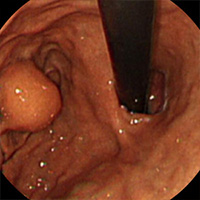

점막하 종양

• 점막하종양 또는 상피하종양은 정상점막으로 덮여 있으며 장관 내강으로 돌출된 병변을 말합니다. 대부분은 무증상으로 내시경 및 방사선 검사에서 우연히 발견되는 경우가 많으며 간혹 출혈, 위장관 폐쇄, 장중첩증 등의 무서운 증상이 나타나는 경우도 있습니다.